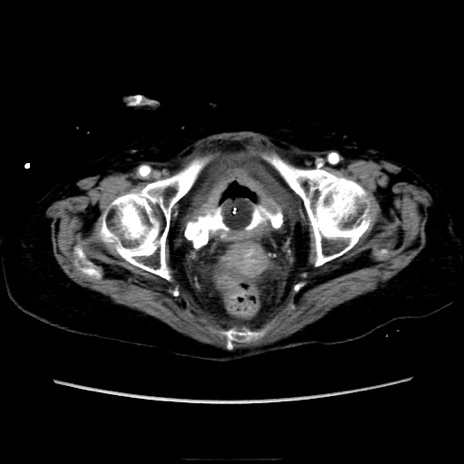

症例40(横断像)

【症例】90歳代女性

【主訴】腹痛・嘔吐

【現病歴】 食欲低下、嘔吐があり昨日他院受診。肺炎と診断され入院となる。入院後より腹部全体に圧痛あり。胃管留置され経過みていたが、症状持続するため、

当院転院となる。

【既往歴】胸椎圧迫骨折、胆石症

【身体所見】腹部:中央に激痛あり、圧痛あり、反跳痛不明

【データ】WBC 17100、CRP 18.82

横断像